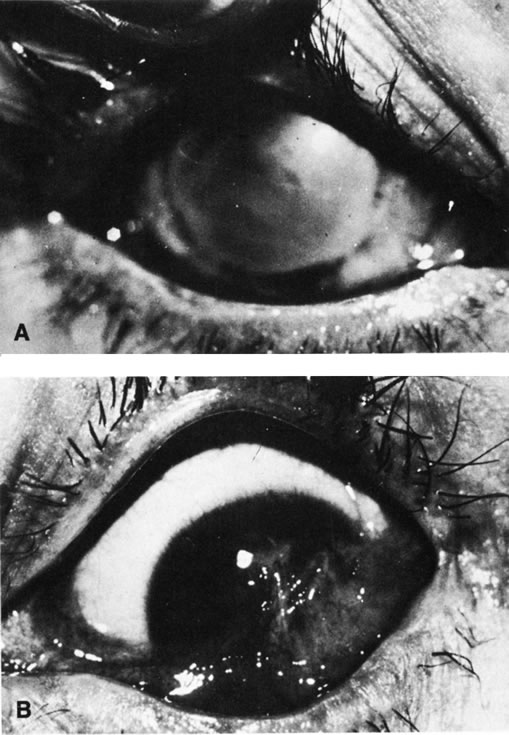

The spectrum of ocular findings in the battered child is vast. Essentially any injury to the eye or adnexa could be due to abuse. An ocular injury may be as mild as periorbital edema or as severe as a ruptured globe. Signs of bilateral ocular trauma suggest inflicted injury because accidents usually involve only one eye. Perhaps one exception is bilateral periocular ecchymosis due to an accidental, single, central forehead trauma (Fig. 6). However, periorbital ecchymosis may also be caused by inflicted trauma with or without injury to the underlying globe. Attempts to date bruises by their color, particularly when the blood is accumulated in the loose skin of the lids, is notoriously unreliable.

Other eye findings such as hyphema and unilateral lens subluxation are usually due to trauma, but rarely have other causes. Subconjunctival hemorrhage is a common finding in child abuse, occurring in 4% to 10% of patients.9,10 Jain and colleagues15 reported a 1.7% incidence of subconjunctival hemorrhage in newborns as a result of the normal birth process. This is transient, and subconjunctival hemorrhage beyond the first 2 weeks of life should be considered suspicious.3 One must also rule out other causes of subconjunctival hemorrhage such as thrombocytopenia. Pertussis can result in severe 360-degree bilateral subconjunctival hemorrhage. Consideration of appropriate diagnostic tests is always important in eliminating explanations other than abuse.

MUNCHAUSEN SYNDROME BY PROXY

Munchausen syndrome by proxy (MSBP) is a form of physical (and emotional) child abuse that occurs when a parent, the mother in over 90% of cases, causes the appearance of an illness by the falsification of history, creation of physical findings, or manipulation of laboratory test results. The most common presentation of MSBP is covert suffocation injury causing the child to have seizures or recurrent apnea. The presenting ocular sign may include subconjunctival hemorrhage that is sometimes associated with petechia of the face and perioral or perinasal injury. The perpetrator may induce vomiting in the child or feed the child substances that cause vomiting or diarrhea. Covert poisoning is also a common form of MSBP, and cases of injection of substances ranging from insulin to feces are well known. Reported ocular manifestations have been numerous and include recurrent conjunctivitis due to instillation of chemicals into the fornices. This has even resulted in corneal scarring with bilateral legal blindness (Fig. 8). Pupil and eye movement abnormalities due to toxic topical or systemic medications, recurrent periorbital cellulitis due to injection of foreign substances around the eye, and even intravenous injection of noxious substances into a child receiving chemotherapy for retinoblastoma have been reported. As a result of recurrent unexplained symptoms, the child may be subjected to multiple invasive diagnostic tests, procedures, and hospitalizations, and the physician ordering the tests becomes an unknowing participant in the battery of the patient. Physicians must be aware of the signs of MSBP that are summarized in Table 4 and may help to reveal the diagnosis.